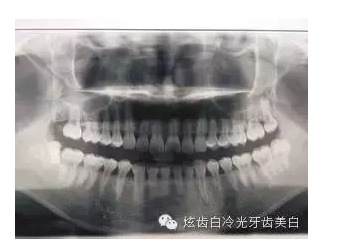

6、X光片檢查:顯示齲壞程度,牙根,牙槽骨的情況。